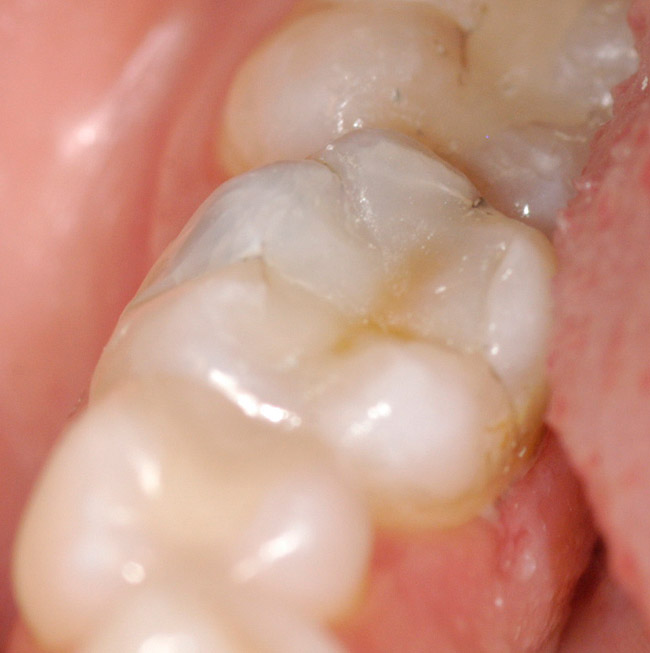

Figure 2  Shows a view of the tooth isolated by the rubber dam. The preparation is complete and the tooth has been total etched for 5 seconds and thoroughly rinsed with water for 15 seconds. The tooth has been blotted dry and a flowable base is being bulk-filled into the deepest portions of the cavity preparation.

Figure 2